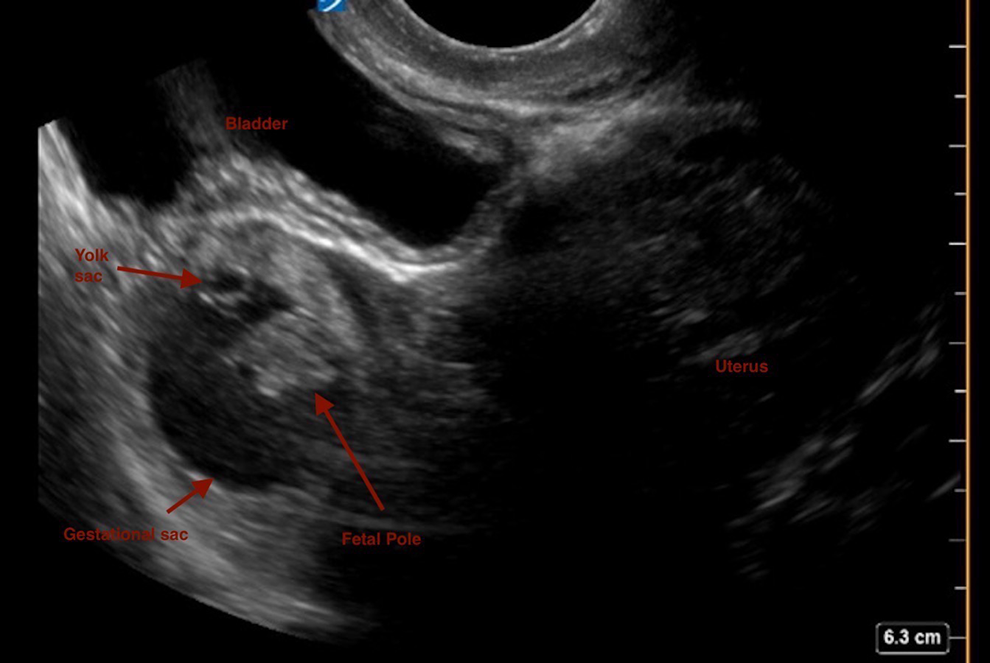

The patient had a positive urine pregnancy test and a serum βhCG resulted at 4979 mIU/mL (negative is <5 mIU/mL). The patient’s transvaginal ultrasound (TVUS) is shown in Figure 1.

Transvaginal ultrasound.

Transvaginal ultrasound of the uterus demonstrates an extrauterine gestational sac and yolk sac with a fetal pole in the left fallopian tube (Figure 2). No fetal cardiac activity was noted.

Transvaginal ultrasound (TVUS) showing ectopic pregnancy, characterized by presence of a yolk sac, gestational sac, and fetal pole in the left adnexa with an empty uterine cavity.

The working diagnosis is an ectopic pregnancy. This is based on the patient’s clinical presentation, history of sexual activity without contraception, history of sexually transmitted illness, lack of menstrual period, elevated serum βhCG, and ultrasound finding of a definitive gestational sac, yolk sac, and fetal pole in the left adnexa, outside of the uterine cavity.